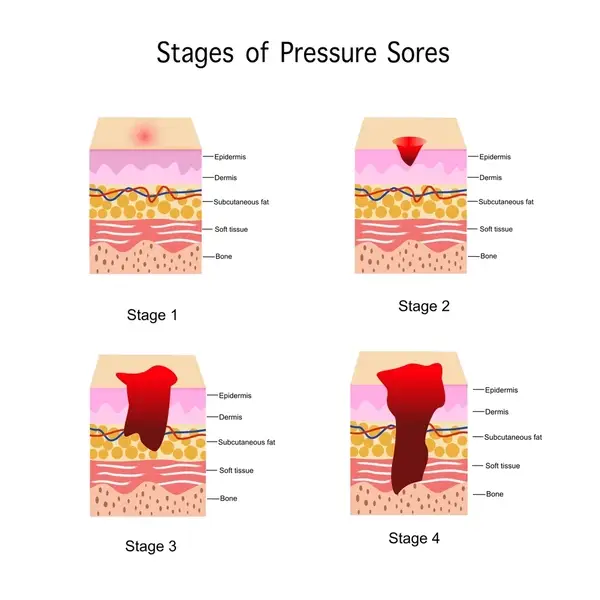

Bed Sores (Pressure Ulcers)

Surgical and reconstructive management of pressure sores for faster healing and reduced recurrence. Flap coverage and wound optimization techniques are used. Focused on patient comfort and recovery.